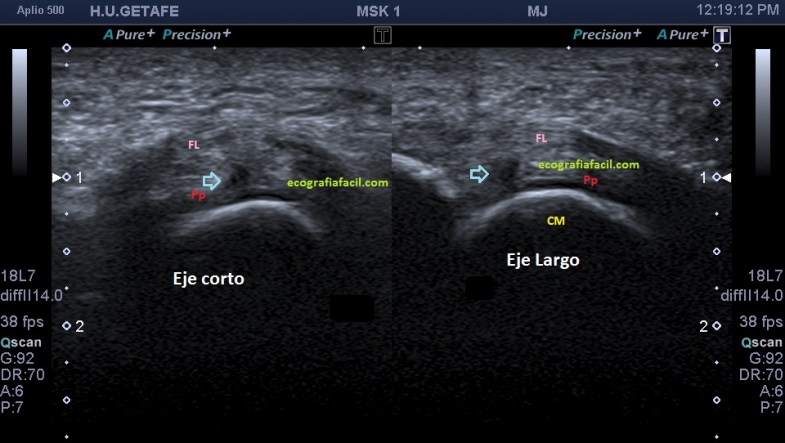

Estudiamos y demostramos la lesión o la normalidad en dos proyecciones, imagen 6, eje largo y eje corto de la zona y podemos comparar siempre con el lado contralateral, previsiblemente sano, dicho todo este conglomerado de ideas…las imágenes:

Marcadas con flecha azul puedes ver un efecto de discontinuidad a nivel de la placa plantar, hipoecogénico e irregular, demostrado en dos proyecciones.